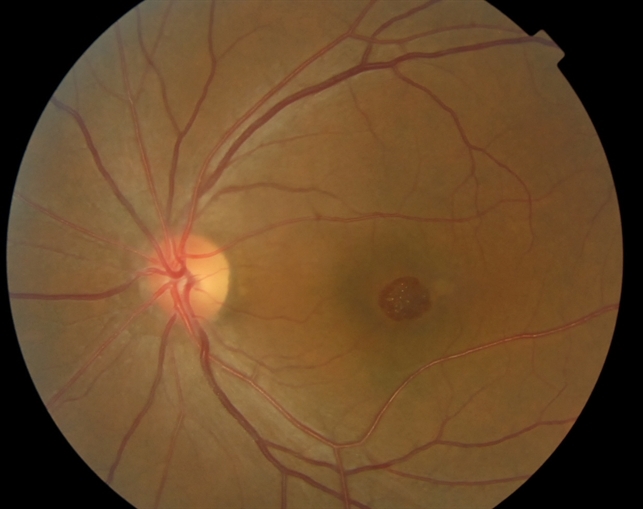

Tamoxifen Retinopathy- Fundus Photo - Retina Image Bank

Source: imagebank.asrs.org

tamoxifen retinopathy fundus retina file imagebank.